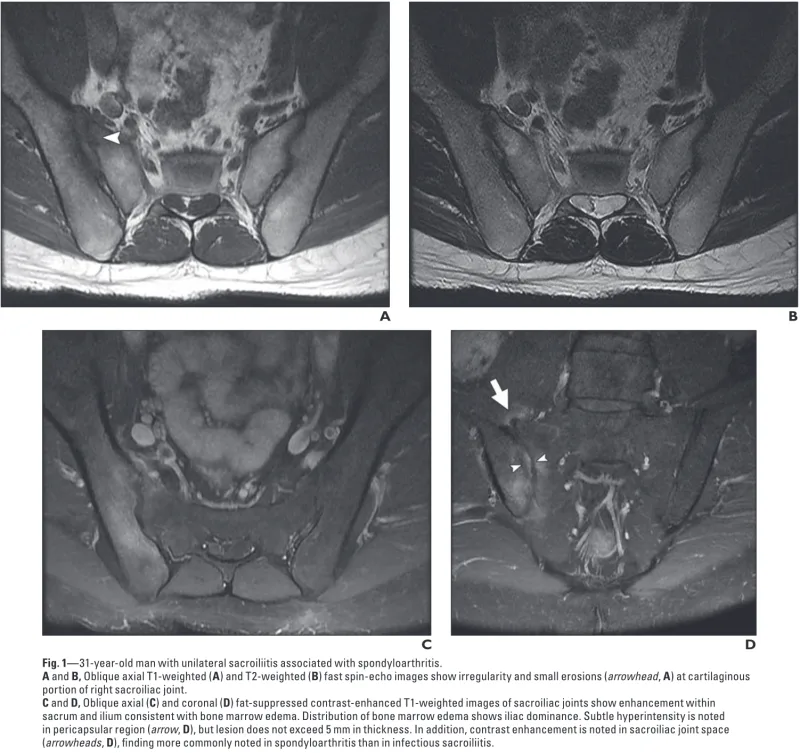

その後, 殿部痛の患者さんの血液検査結果を確認.

CRPが1.46 mg/dL(基準値0.3未満)と炎症反応が陽性.

炎症性疾患による殿部痛を疑い, MRIをオーダーしました.

右の仙腸関節部が, T1強調画像(A)では黒く, T2強調画像(B)では白く写っています.

MRIでは, 疼痛側の仙腸関節に明らかな炎症性変化を認めました.

何らかの原因による仙腸関節炎が殿部痛の原因と判断.

仙腸関節炎の代表的疾患としては脊椎関節炎が挙げられますが, 急性発症という点が一致しません.

一方, 細菌感染による仙腸関節炎は見逃してはならないものの, 糖尿病や悪性腫瘍など, 明らかな易感染性因子は認めませんでした.

原因は特定できず, 消炎鎮痛薬ジクロフェナクを処方し, 1週間後に再評価することに.

効果が乏しければ早めに再診するよう説明しました.